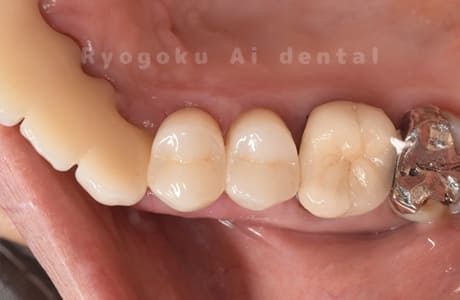

Case37

-

- 原因

- 補綴物二次カリエス

- 治療内容

- 24番ダイレクトボンディング、25番セラミックインレー修復、26・27番セラミッククラウン修復

- 治療費用

- 387,000円

歯がしみるとのことでご来院された患者様です。銀歯の中が大きく虫歯になっておりました。セラミックの材料で再治療を行いました。

<リスク・副作用>

過度の咬合や衝撃で割れることがあります。術後は痛み、腫れ、痺れなどの副作用が生じる場合があります。